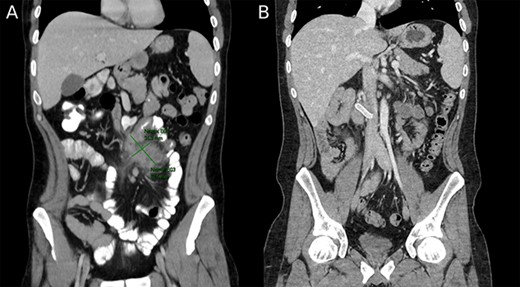

The surgery commenced with laparoscopy under general anesthesia. Many adhesions from previous surgeries and malrotation were noted, with the colon found in the left side of the abdominal cavity and the small intestine on the right. Due to the degree of adhesions and malrotation, the procedure was converted to an open approach through a midline incision. The section of the ileum causing the obstruction was visualized in the distal ileum, which included severe stenosis, with nearly 8-cm dilated small bowel proximal to the stenosis (Fig. 2).

Intraoperative images depicting malrotation of the inflamed intestine (A) and a 35-cm segment of the distal terminal ileum that was resected (B).

A Heineke–Mikulicz strictureplasty was performed on the proximal stricture. A length of 35 cm of the distal terminal ileum was resected and a side-to-side anastomosis to the proximal small bowel was performed.